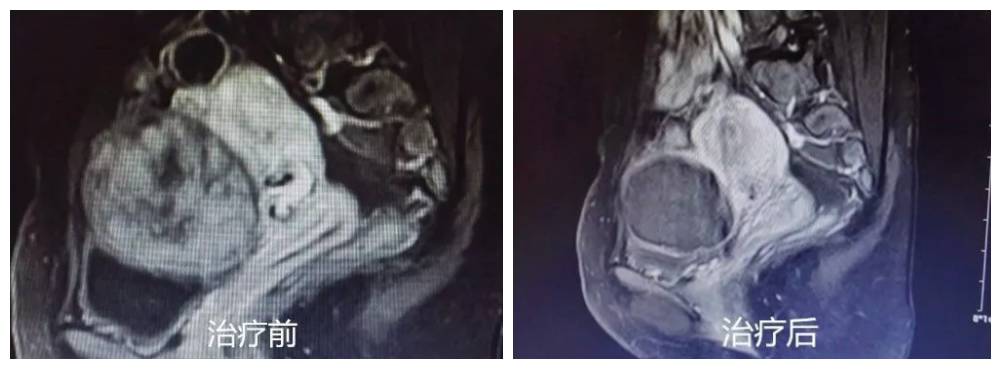

她经过医生介绍到来到市妇幼保健院柳东分院 妇科海扶聚焦超声治疗区进行了常规术前检查(术前超声定位、核磁评估、拟定方案),评估病情后进行高强度聚焦超声消融治疗(海扶刀)。治疗过程非常顺利,仅用26分钟就完成了直径5cm的肌瘤消融。术后恢复好,复查核磁显示子宫肌瘤消融率达到99%。